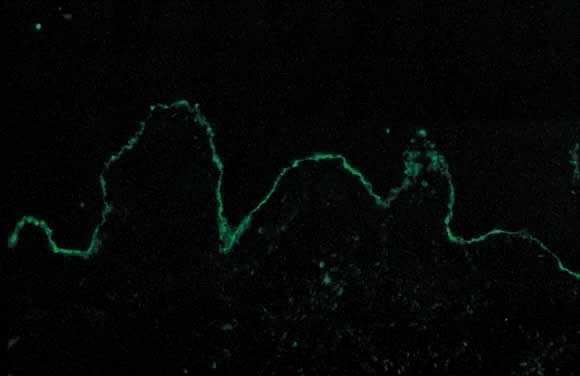

Fig. 11. Polymorphic eruption of pregnancy direct immunofluorescence: granular band of C3 along the skin basement membrane zone.

Dermatopathology shows variable epidermal spongiosis with a perivascular inflammatory infiltrate in the dermis composed of lymphocytes, histiocytes, and a variable number of eosinophils. Direct immunofluorescence (DIF) is negative for a linear band of C3 or IgG along the skin dermoepidermal junction (DEJ); however, there have been reports of deposition of IgM, C3, and IgA along the DEJ and blood vessels on DIF (Fig. 11).15,18 Differential diagnosis of PEP includes pemphigoid gestations (PG), contact dermatitis, drug eruption, and viral exanthems. DIF of skin is necessary to differentiate PEP from PG. The clinical course of PEP is usually self-limiting, with a mean duration of 6 weeks. Pruritus is most severe in the first week of onset, with spontaneous remission occurring within days of parturition. Maternal and fetal mortalities are unaffected. PEP rarely occurs in subsequent pregnancies; however, a few cases of reoccurrence are reported in the literature.13 Treatment is symptomatic relief of pruritus with topical corticosteroids of low- to mid-potency (use of ultra-high-potency corticosteroids for an extensive period of time should be avoided) and pregnancy category B antihistamines such as loratadine and cetirizine. Hydroxyzine and diphenhydramine are pregnancy category C antihistamines that have been used to relieve pruritus. In cases of severe pruritus unresponsive to conservative measures, systemic corticosteroid administration or induced delivery is considered.

Dermatopathology of PG shows subepidermal vesicle formation with focal necrosis of keratinocytes. The dermis shows papillary edema and a perivascular infiltrate consisting mainly of eosinophils and few lymphocytes. An occasional finding on histopathology is the alignment of eosinophils along the dermoepidermal junction. DIF shows a characteristic linear band of C3 along the skin basement membrane zone of patients with PG (Fig. 14). Linear C3 deposition on DIF is diagnostic of PG in the correct clinical setting and is used to differentiate PEP from PG.28 Using this method, about 25% of cases also present with IgG deposits along the basement membrane zone. Indirect immunofluorescence (IIF) demonstrates the “PG factor,” which consists of circulating IgG complement-fixing anti-basement membrane zone antibodies in serum of patients with PG. Complement-activated IIF using monoclonal antibodies directed against IgG1 demonstrates this factor in all PG patients.29 Clinically, titers of PG factor do not correlate with disease severity. The PG factor is an IgG directed against a 180-kd hemidesmosomal (transmembrane) component of the basement membrane zone.30 Electron microscopy also demonstrates the C3 and IgG deposits in the lamina lucida.31

Fig. 14. Pemphigoid gestationis by direct immunofluorescence: linear band of C3 along basement membrane zone of the skin.